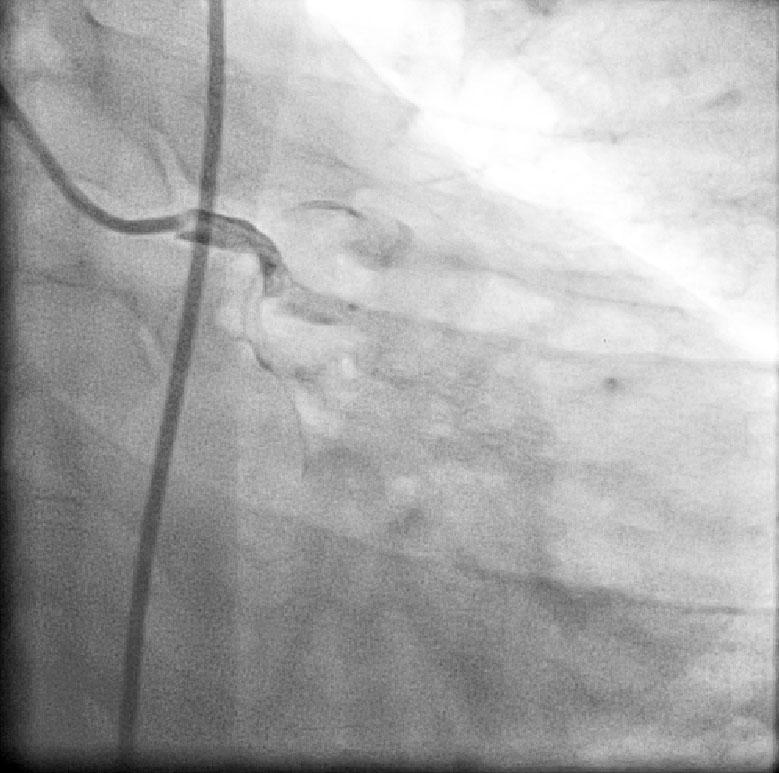

CABG in Kawasakis with Coronary Aneurysms

Ring Calcification In Kawasaki disease

Angiogram prior to Primary PTCA